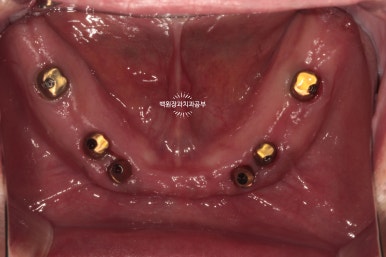

왼쪽이 위턱의 임시치아들이고, 오른쪽이 아래턱의 임시치아들입니다.

이 임시치아를 빼보겠습니다. 그럼 맞춤형 지대주가 보이겠죠?

눈치 빠른 분은 아셨을거에요!! 위가 위턱, 아래가 아래턱입니다.

왜냐?! 지대주가 위가 8개, 아래가 6개잖아요~~ 제가 올려드렸던 치과용 파노라마를 확인해보세요!

환자분의 구강 내에 맞춤형 지대주를 연결하고 임시치아를 붙여드렸습니다.

어디서 많이 본 것 같은데...?

맞습니다! 환자분 입 안에 만들어온 맞춤형 지대주를 그대로 연결해드렸습니다.

아래가 기공소에서 받아왔던 상태이고, 위 사진이 받아온 맞춤형 지대주를 입 안에서 모두 연결한 상태입니다.